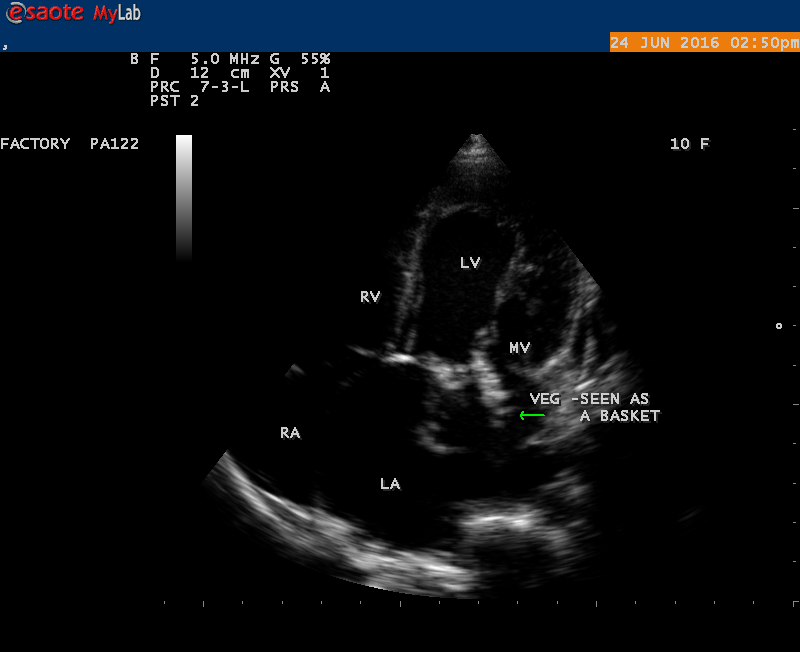

The most common and direct evidence of infective endocarditis is the vegetation and it begins as a microscopic focus of infection and gradually grows into a conspicuous mass. It is typically an irregularly shaped, highly mobile, echogenic mass attached to the free edge of a valve leaflet ( most commonly at the coaptation line) and tends to develop on the ‘upstream’ side of the valve leaflets ( ie, the ventricular side of aortic valve and the atrial side of mitral and tricuspid valves. They may be seesile or pedunculated, but usually has an oscillating or fluttering motion, a typical feature of most vegetations. Vegetation move with the leaflet in a more chaotic (‘oscillating’) manner and it may prolapse through the valve into the LV (left ventricle) as it opens as shown in Figures 3, 4 and 16 and into LA (left atrium) as it closing (Figure 5 and 6) . The mass of vegetation is typically homogeneous with echogenicity similar to that of the myocardium. The infectious process often alter the valvular structure and function. Extensive involvement of the leaflet may result in chordal rupture, leading to severe regurgitation as shown in Figure 21 . Direct and typical signs of RMCT (ruptured mitral chordate tendineae) were chain-flail or whiplash-like changes and had an incidence of 86.7%, causing severe regurgitation and mitral chordal rupture is the leading cause of flail mitral leaflet[30]. A large vegetation may obstruct the valve orifice as shown in Figure 1 and 2 , sometimes termed as “obstructive-type bacterial endocarditis” and producing a functional valve stenosis ( Ping-Pong mitral stenosis [31]) similar to left atrial myxoma as shown in Figure 29.

The shape of vegetation varies in this child as ‘popcorn’ like (Figures 1,3 and 4 ), rod-shaped (Figure ), basket shaped (Figure 7 )[33-Figure 13.3], ‘baby in hand’ appearance (Figure 18), ‘cucumber shaped (Figure 2 ) and a ‘bunch of plantain’appearance (Figure 33 ), ring shaped (Figure 19 }, bileaflet structure (Figure 9 )with bileaflet MR jet as shown in Figure 10 . and kissing forms (Figure 13 - parasternal long axis view, Figure 14 - apical four chamber view and Figure 15 - short axis view)